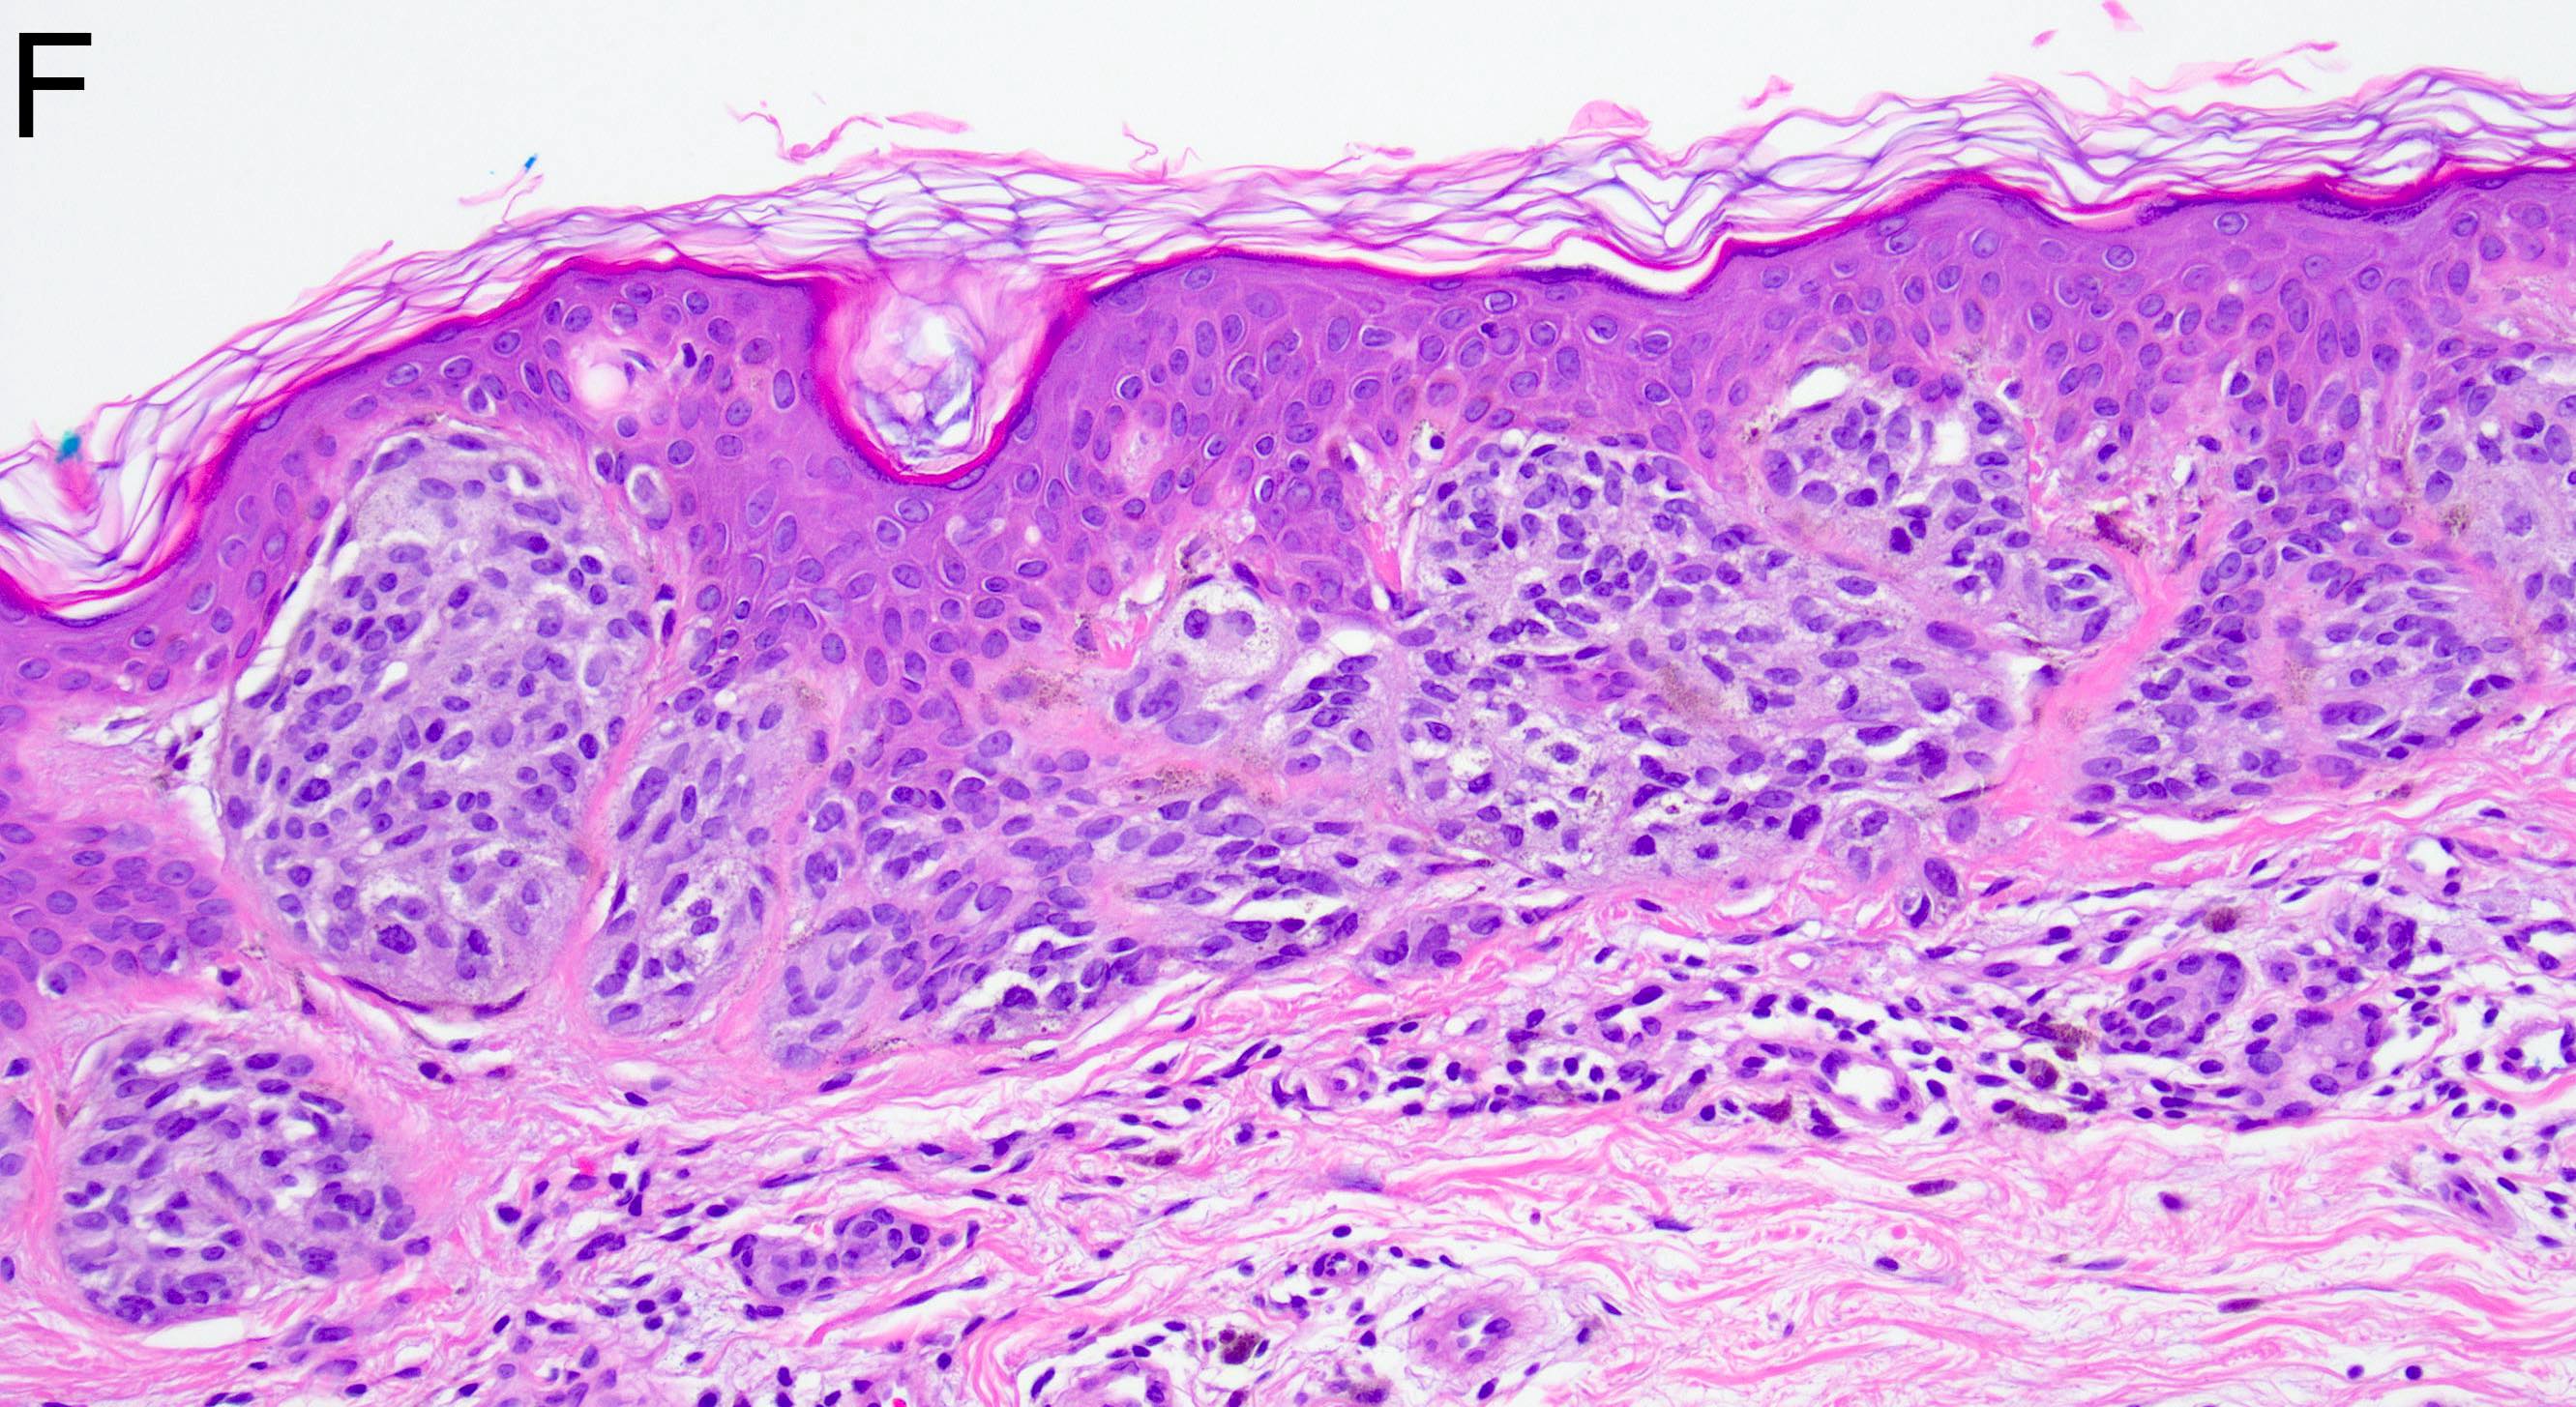

- Melanocytic nevi of the scalp (Am J Dermatopathol 2016;38:867):

- Melanocytes can be enlarged with irregular nuclei but atypia should be uniform throughout the nevus

- May contain large irregular nests in close proximity to one another

- Lentiginous growth may be prominent

- Pagetoid spread is a common feature

- Lesion can have broad junctional involvement and involve adnexa

- Single cell dispersion can be seen at lateral edges

- Lateral circumscription and maturation should be maintained, however symmetry may be lost (Am J Dermatopathol 2016;38:867)

- Prominent stromal fibrotic response can be seen

Microscopic (histologic) images